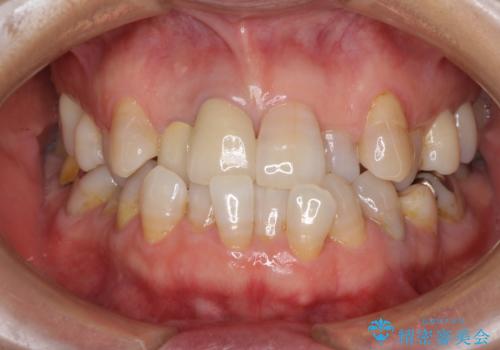

変色した前歯のオールセラミック治療

気になっていた変色が改善され、患者様には大変満足していただきました。